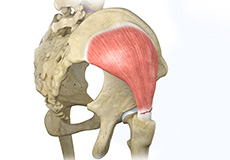

Gluteus Tendon Tear

The gluteal muscles (situated in the buttocks) are necessary for the stability and movement of the hip joints. The tendons of two gluteal muscles (gluteus medius and gluteal minimus) are attached at the outer hip region and are often called the “rotator cuff of the hip.” These tendons may be subject to injury or tearing due to various reasons. Since these gluteal muscles are involved in abduction (movement of your leg away from the midline of the body), the tears are also called abductor tendon tears.

Gluteus Medius Tear

A gluteus medius tear is the partial or complete rupture of the gluteus medius muscle due to severe muscle strain.

Hip Abductor Tears

Hip abductors are a major group of muscles found in the buttocks. It includes the gluteus maximus, gluteus medius, gluteus minimus, and tensor fascia lata muscles.

Arthroscopic Gluteus Medius Tendon Repair

Arthroscopic gluteus medius tendon repair is a minimally invasive surgical procedure employed for the treatment of a gluteus medius tendon tear, when the tear does not respond to conservative treatment.